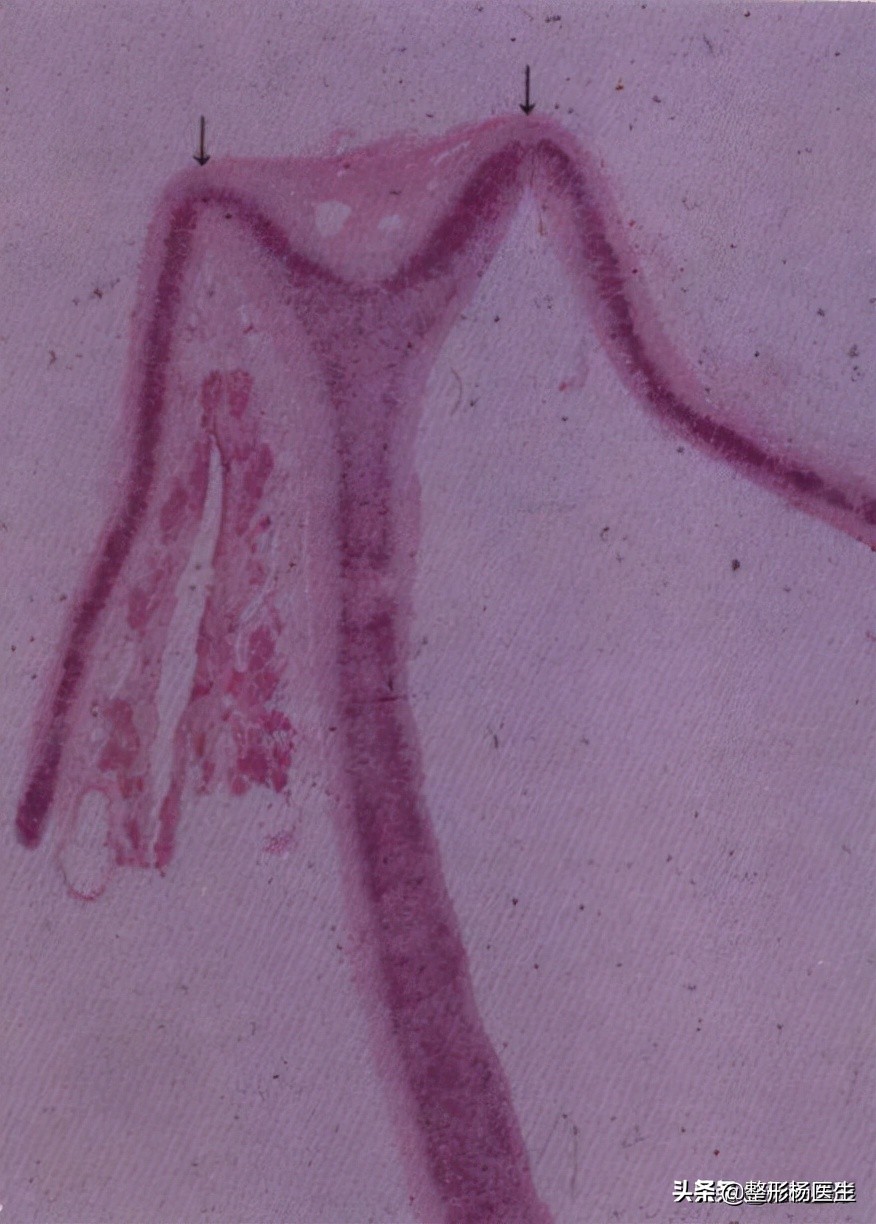

显微镜下的侧鼻软骨和鼻中隔截面